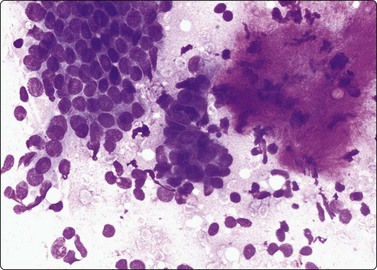

image image

Fig. 7.15 Regenerative epithelial atypia in mastitis

(A) Atypical, reactive/regenerating epithelial cells with a background of histiocytes, inflammatory cells and debris (MGG, HP); (B) Corresponding tissue section (H&E, IP).